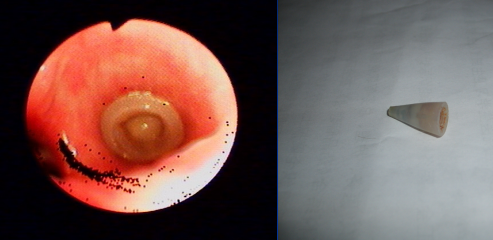

6、取出的异物“苍耳子”:

7、取出的部分异物图片展示: